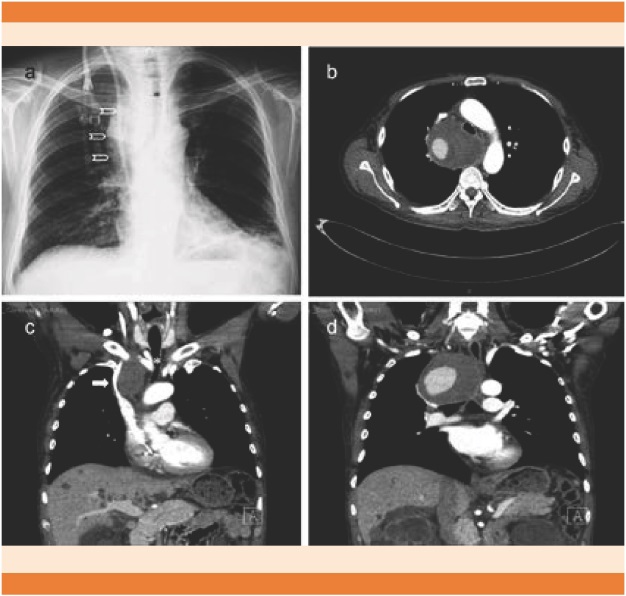

La radiografía de tórax (Figura 6) es el estudio de imagen inicial y es primordial para decidir el siguiente paso.14 La inyección de medio de contraste para observar la vena cava (cavografía) es el patrón de referencia para confirmar el grado y nivel de la obstrucción.4 A partir de los estudios de tomografía con medio de contraste, la cavografía prácticamente no se realiza en la actualidad; sin embargo, es indiscutible su utilidad práctica para valorar la colocación de endoprótesis.15

La tomografía de tórax convencional con contraste o multicorte3,16 es hoy día el estudio de elección y el más utilizado, porque además de confirmar el diagnóstico, permite valorar el nivel y la gravedad de la obstrucción. El patrón de venas colaterales por tomografía axial computada contrastada de tórax (Figura 7) es un referente importante para el diagnóstico de síndrome de la vena cava superior con sensibilidad y especificidad de 96 y 92%, respectivamente.17,18 Otras ventajas de la tomografía son determinar el sitio más seguro y adecuado para la toma de biopsia, realizar el plan quirúrgico y el marcaje del área para radioterapia.

Figura 7 Tomografía de tórax contrastada de una paciente de 62 años de edad con timoma epitelioide. A y B. Compresión casi total de la vena cava superior por arriba de la vena ácigos (flecha). C. Venas colaterales dilatadas en tórax. D. Reconstrucción tridimensional con múltiples venas torácicas colaterales.